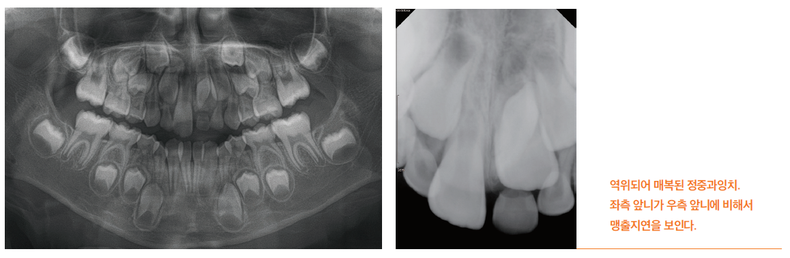

과잉치는 성별과 인종에 따라 발생 빈도가 다르며, 여아보다 남아에서 약 2배 더 흔하게 발생합니다. 또한 서양인보다 동양인에서 발생률이 다소 높게 보고되고 있습니다. 전체 과잉치의 80-90% 이상이 아래턱보다는 위턱에서 주로 발견되며, 특히 위턱의 앞니 중앙 부위에서 가장 흔하게 나타납니다. 이 부위에 생기는 과잉치를 정중과잉치(me-siodens)라고 부릅니다. 그 외 부위에서도 발견될 수 있습니다.과잉치는 맹출 방향에 따라 정상방향, 역위(inverted), 수평위(hori-zontal) 등으로 구분할 수 있으며, 1/4 정도만이 자발적으로 잇몸 밖으로 맹출합니다. 대부분의 과잉치는 턱뼈 내에 매복된 상태로 남아 있습니다.

과잉치는 방치할 경우 여러 가지 문제를 일으킬 수 있어 세심한 관찰과 적절한 치료가 필요합니다. 과잉치가 가장 흔히 일으키는 문제는 영구치의 맹출 방해입니다. 과잉치가 있으면 정상적인 영구치가 제대로 올라오지 못할 수 있으며, 특히 앞니 부위에 매복되어 있는 정중과잉치는 위 영구치 앞니가 정상적으로 나오는 것을 막아 치아 배열에 문제를 일으킬 수 있습니다. 또한 앞니 사이에 위치한 과잉치는 두 앞니를 밀어내어 치아 사이에 틈을 만들 수 있는데, 이를 정중이개라고 하며 심미적인 문제를 야기할 수 있습니다.